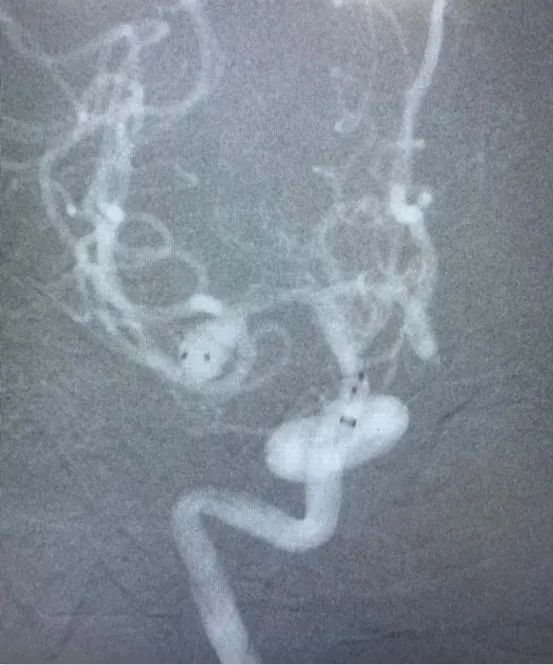

近日,省人民醫(yī)院神經(jīng)外科為一位高齡動脈瘤患者施行了介入治療,成功栓塞了破裂的大腦中動脈瘤?;颊咭蛲话l(fā)暈厥后頭痛不適入院,急診行顱腦CT檢查提示蛛網(wǎng)膜下腔出血,行顱腦CTA檢查后證實患者存在右側(cè)大腦中動脈瘤?;颊吒啐g,既往基礎(chǔ)病多,高血壓病、糖尿病、冠心病、雙側(cè)頸動脈硬化、雙側(cè)腹股溝疝術(shù)后等,手術(shù)風(fēng)險較大,經(jīng)家屬簽字同意后,當(dāng)日急診全麻下行“右側(cè)大腦中動脈瘤介入栓塞術(shù)”,術(shù)中見血管迂曲明顯,導(dǎo)管到位艱難,經(jīng)過努力,手術(shù)順利結(jié)束。術(shù)后予多次腰椎穿刺術(shù)釋放血性腦脊液,患者頭痛頭暈癥狀漸緩解?;颊咦≡褐委?/span>10天后順利康復(fù)出院,未留后遺癥。

動脈瘤主要有兩種治療方式:開顱手術(shù)和介入栓塞。兩種方法比較,介入栓塞手術(shù)時間短、康復(fù)快、不需開顱、可同時治療多個動脈瘤,適合高齡、分級高的患者,其中血管內(nèi)彈簧圈栓塞術(shù)是顱內(nèi)動脈瘤最常見的一種介入治療方式,隨著介入新材料、技術(shù)的不斷進(jìn)步,介入栓塞的優(yōu)勢日漸明顯。